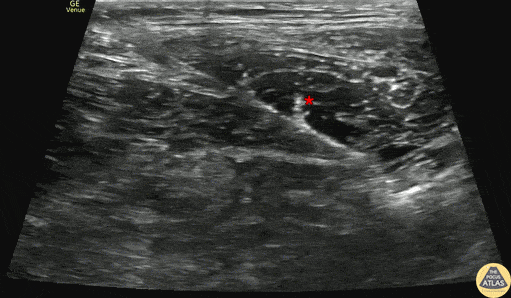

90s F presented with lower extremity pain after mechanical trip and fall at home. Radiographs demonstrated a subtrochanteric femur fracture. The patient had significant pain after arrival and so a fascia iliaca block was performed. The block is shown here, with the needle entering from the lateral aspect (screen left), depositing anesthetic in the fascia iliaca plane, just deep to the sartorius muscle (*). The patient had improvement of her pain rapidly after the block and was admitted for surgery. Dr. Daniel Fuchs, PGY2 Denver Health Residency in Emergency Medicine